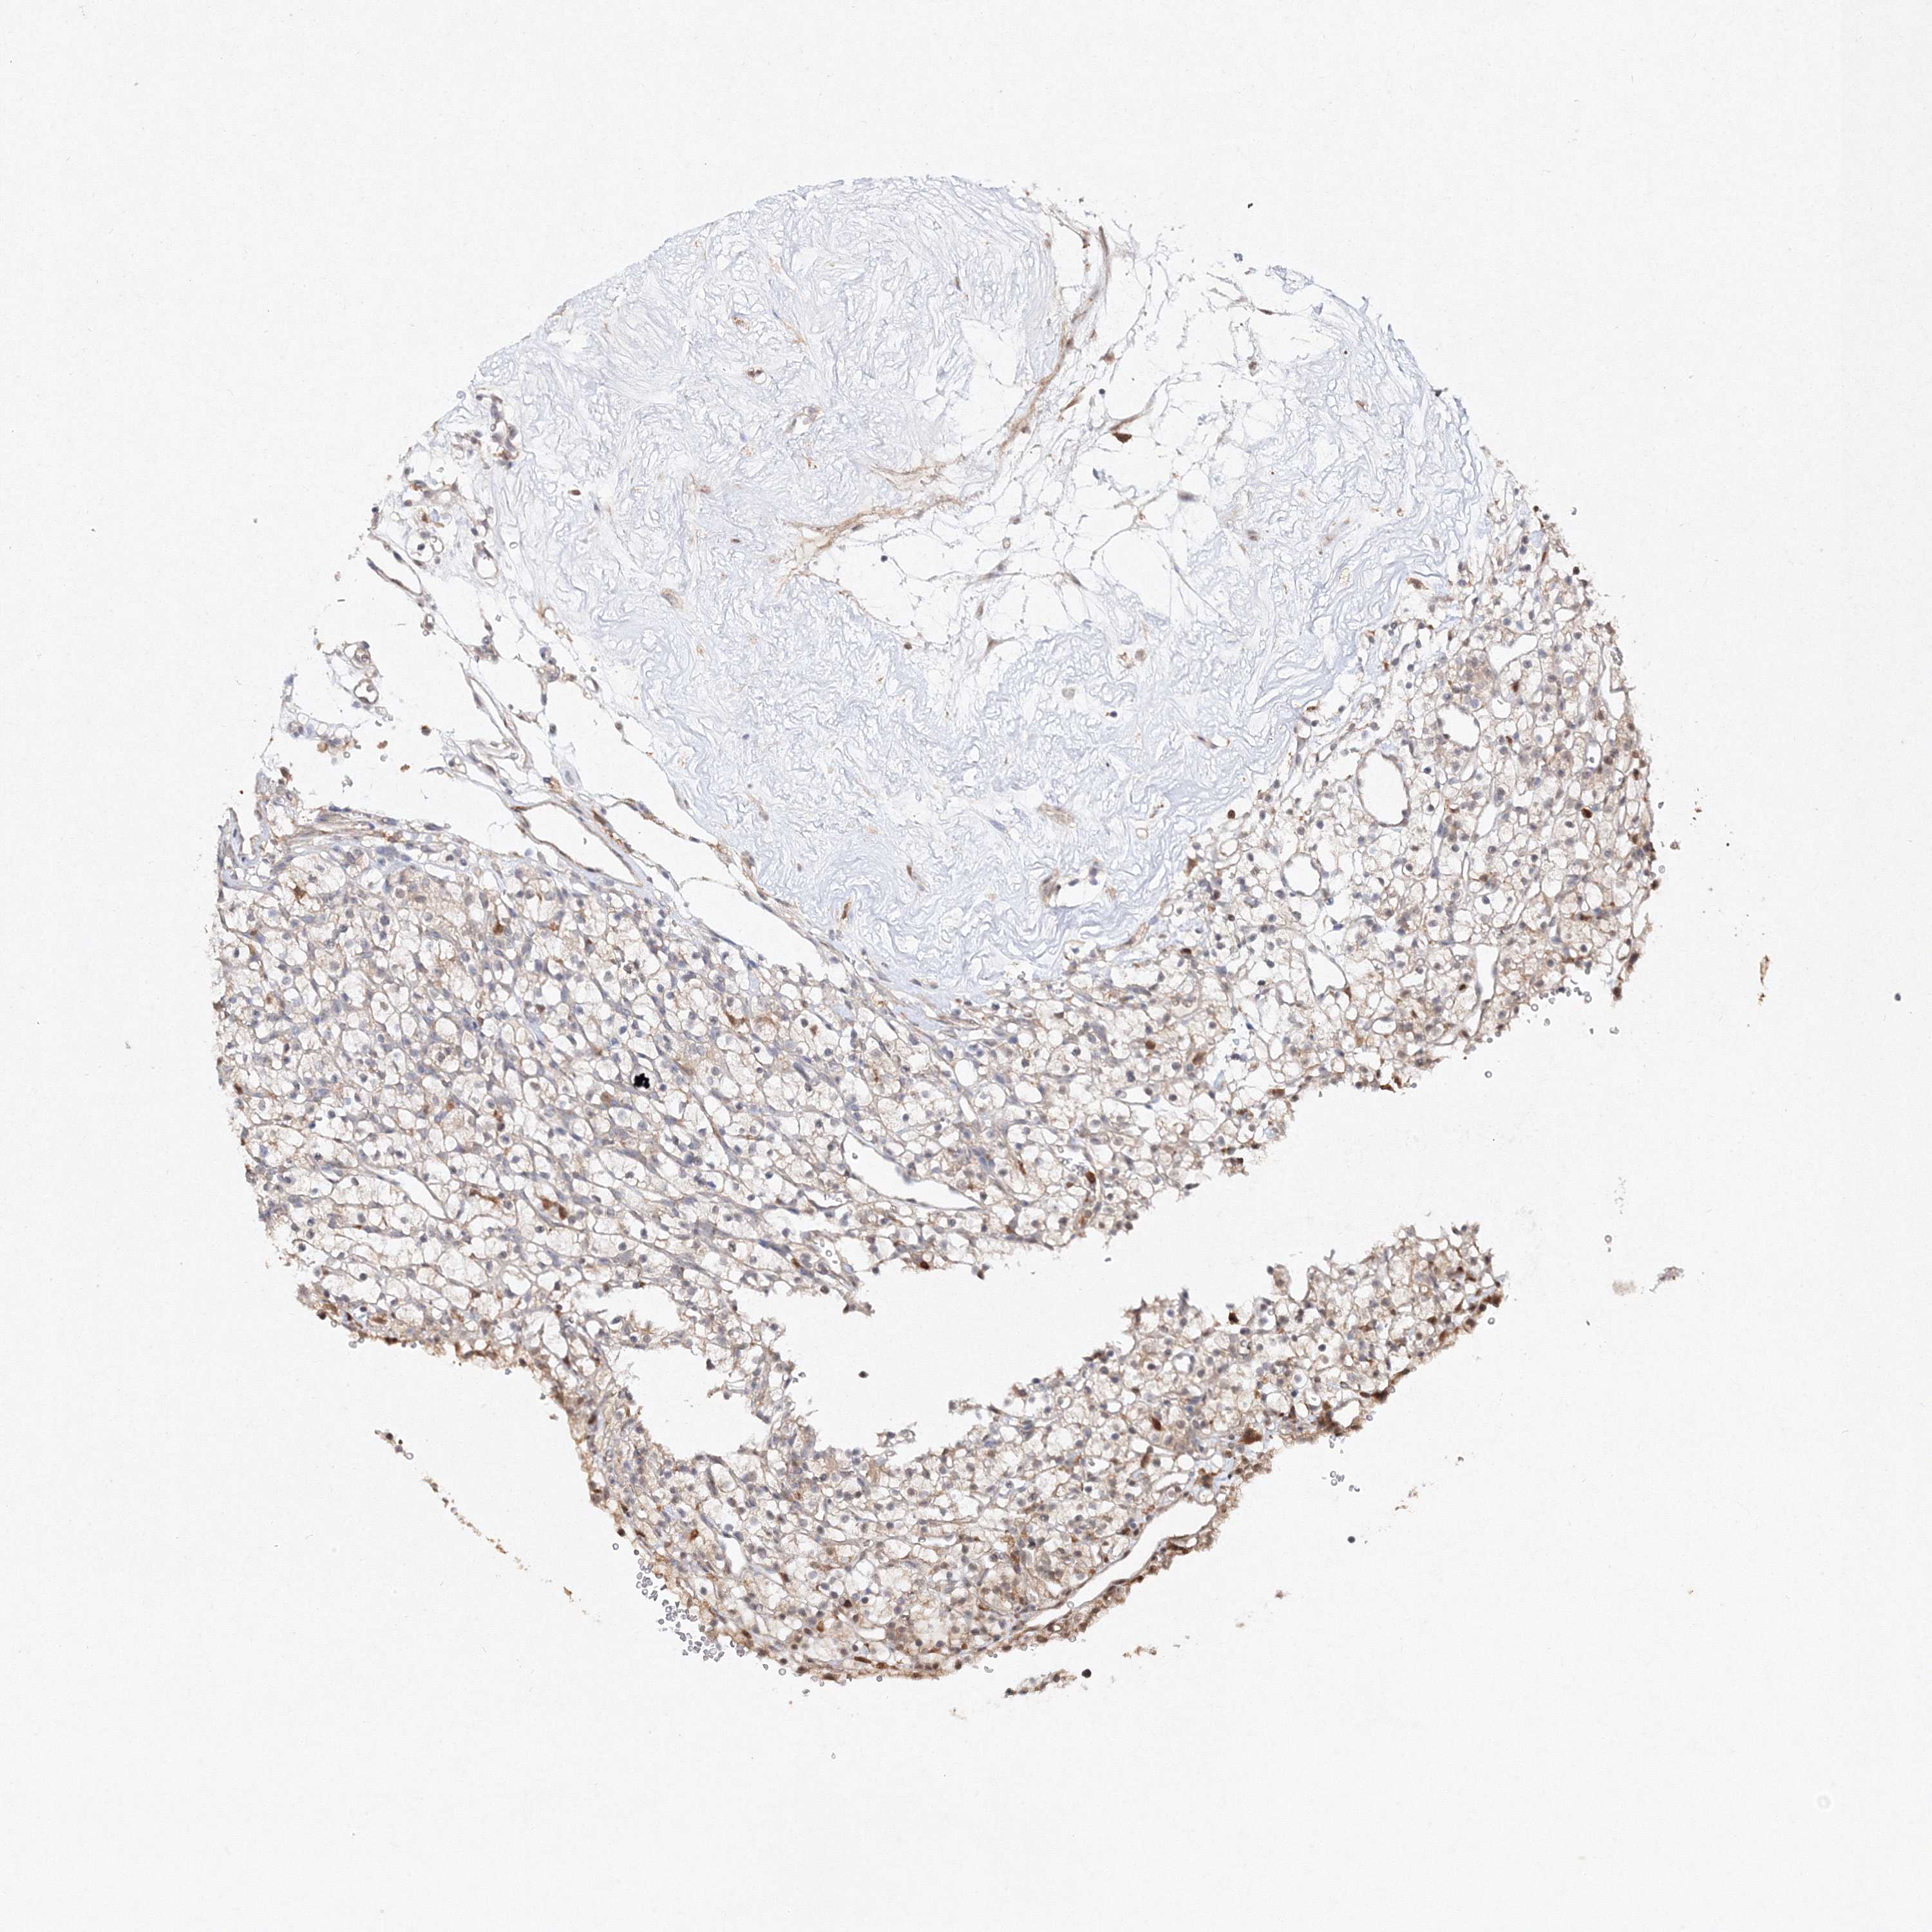

KIDNEY RENAL CLEAR CELL CARCINOMA (VALIDATION) - Interactive survival scatter ploti

The Survival Scatter plot shows the clinical status (i.e. dead or alive) for all individuals in the patient cohort, based on the same data that underlies the corresponding Kaplan-Meier plots. Patients that are alive at last time for follow-up are shown in blue and patients who have died during the study are shown in red.

The x-axis shows the expression levels (FPKM) of the investigated gene in the tumor tissue at the time of diagnosis. The y-axis shows the follow-up time after diagnosis (years). Both axes are complimented with kernel density curves demonstrating the data density over the axes. The top density plot shows the expression levels (FPKM) distribution among dead (red) and alive patients (blue). The right density plot shows the data density of the survived years of dead patients with high and low expression levels respectively, stratified using the cutoff indicated by the vertical dashed line through the Survival Scatter plot. This cutoff is automatically defined based on the FPKM cutoff that minimizes the p-score. The cutoff can be changed by dragging the vertical line or by entering a cutoff value in the square labeled "Current cut-off".

Under the Survival Scatter plot the p-score landscape (black curve; left axis) is shown together with dead median separation (red curve; right axis). Dead median separation is the difference in median mRNA expression between patients who have died with high and low expression, respectively. It is calculated as follows: median FPKM expression of dead patients with high expression - median FPKM expression of dead patients with low expression. This is intended to aid the user in visually exploring custom cutoffs and the associated p-scores and dead median separation.

Individual patient data is displayed and can be filtered by clicking on one or more of the category buttons on the top of the page. Categories describing expression level and patient information include: high, low, alive, dead, female, male and tumor stages. The scale of the x-axis can be toggled between linear and log-scale by clicking on the "x log" button. Mouse-over function shows TCGA ID, patient information and mRNA expression (FPKM) for each patient.

& Survival analysisi

Kaplan-Meier plots summarize results from analysis of correlation between mRNA expression level and patient survival. Patients were divided based on level of expression into one of the two groups "low" (under cut off) or "high" (over cut off). X-axis shows time for survival (years) and y-axis shows the probability of survival, where 1.0 corresponds to 100 percent.

S100A11 is validated prognostic, high expression is unfavorable in Kidney Renal Clear Cell Carcinoma (validation)

Best expression cut offi

Based on the FPKM value of each gene, patients were classified into two groups and association between prognosis (survival) and gene expression (FPKM) was examined. The best expression cut-off refers the FPKM value that yields maximal difference with regard to survival between the two groups at the lowest log-rank P-value. Best expression cut-off was selected based on survival analysis .

When clicking on this number, the vertical dashed line indicating cut-off, the interactive survival plot, and the Kaplan-Meier curve will be adjusted to show results based on the best expression cut-off.

: 987.74

Average pTPM 833.5

Number of samples 100